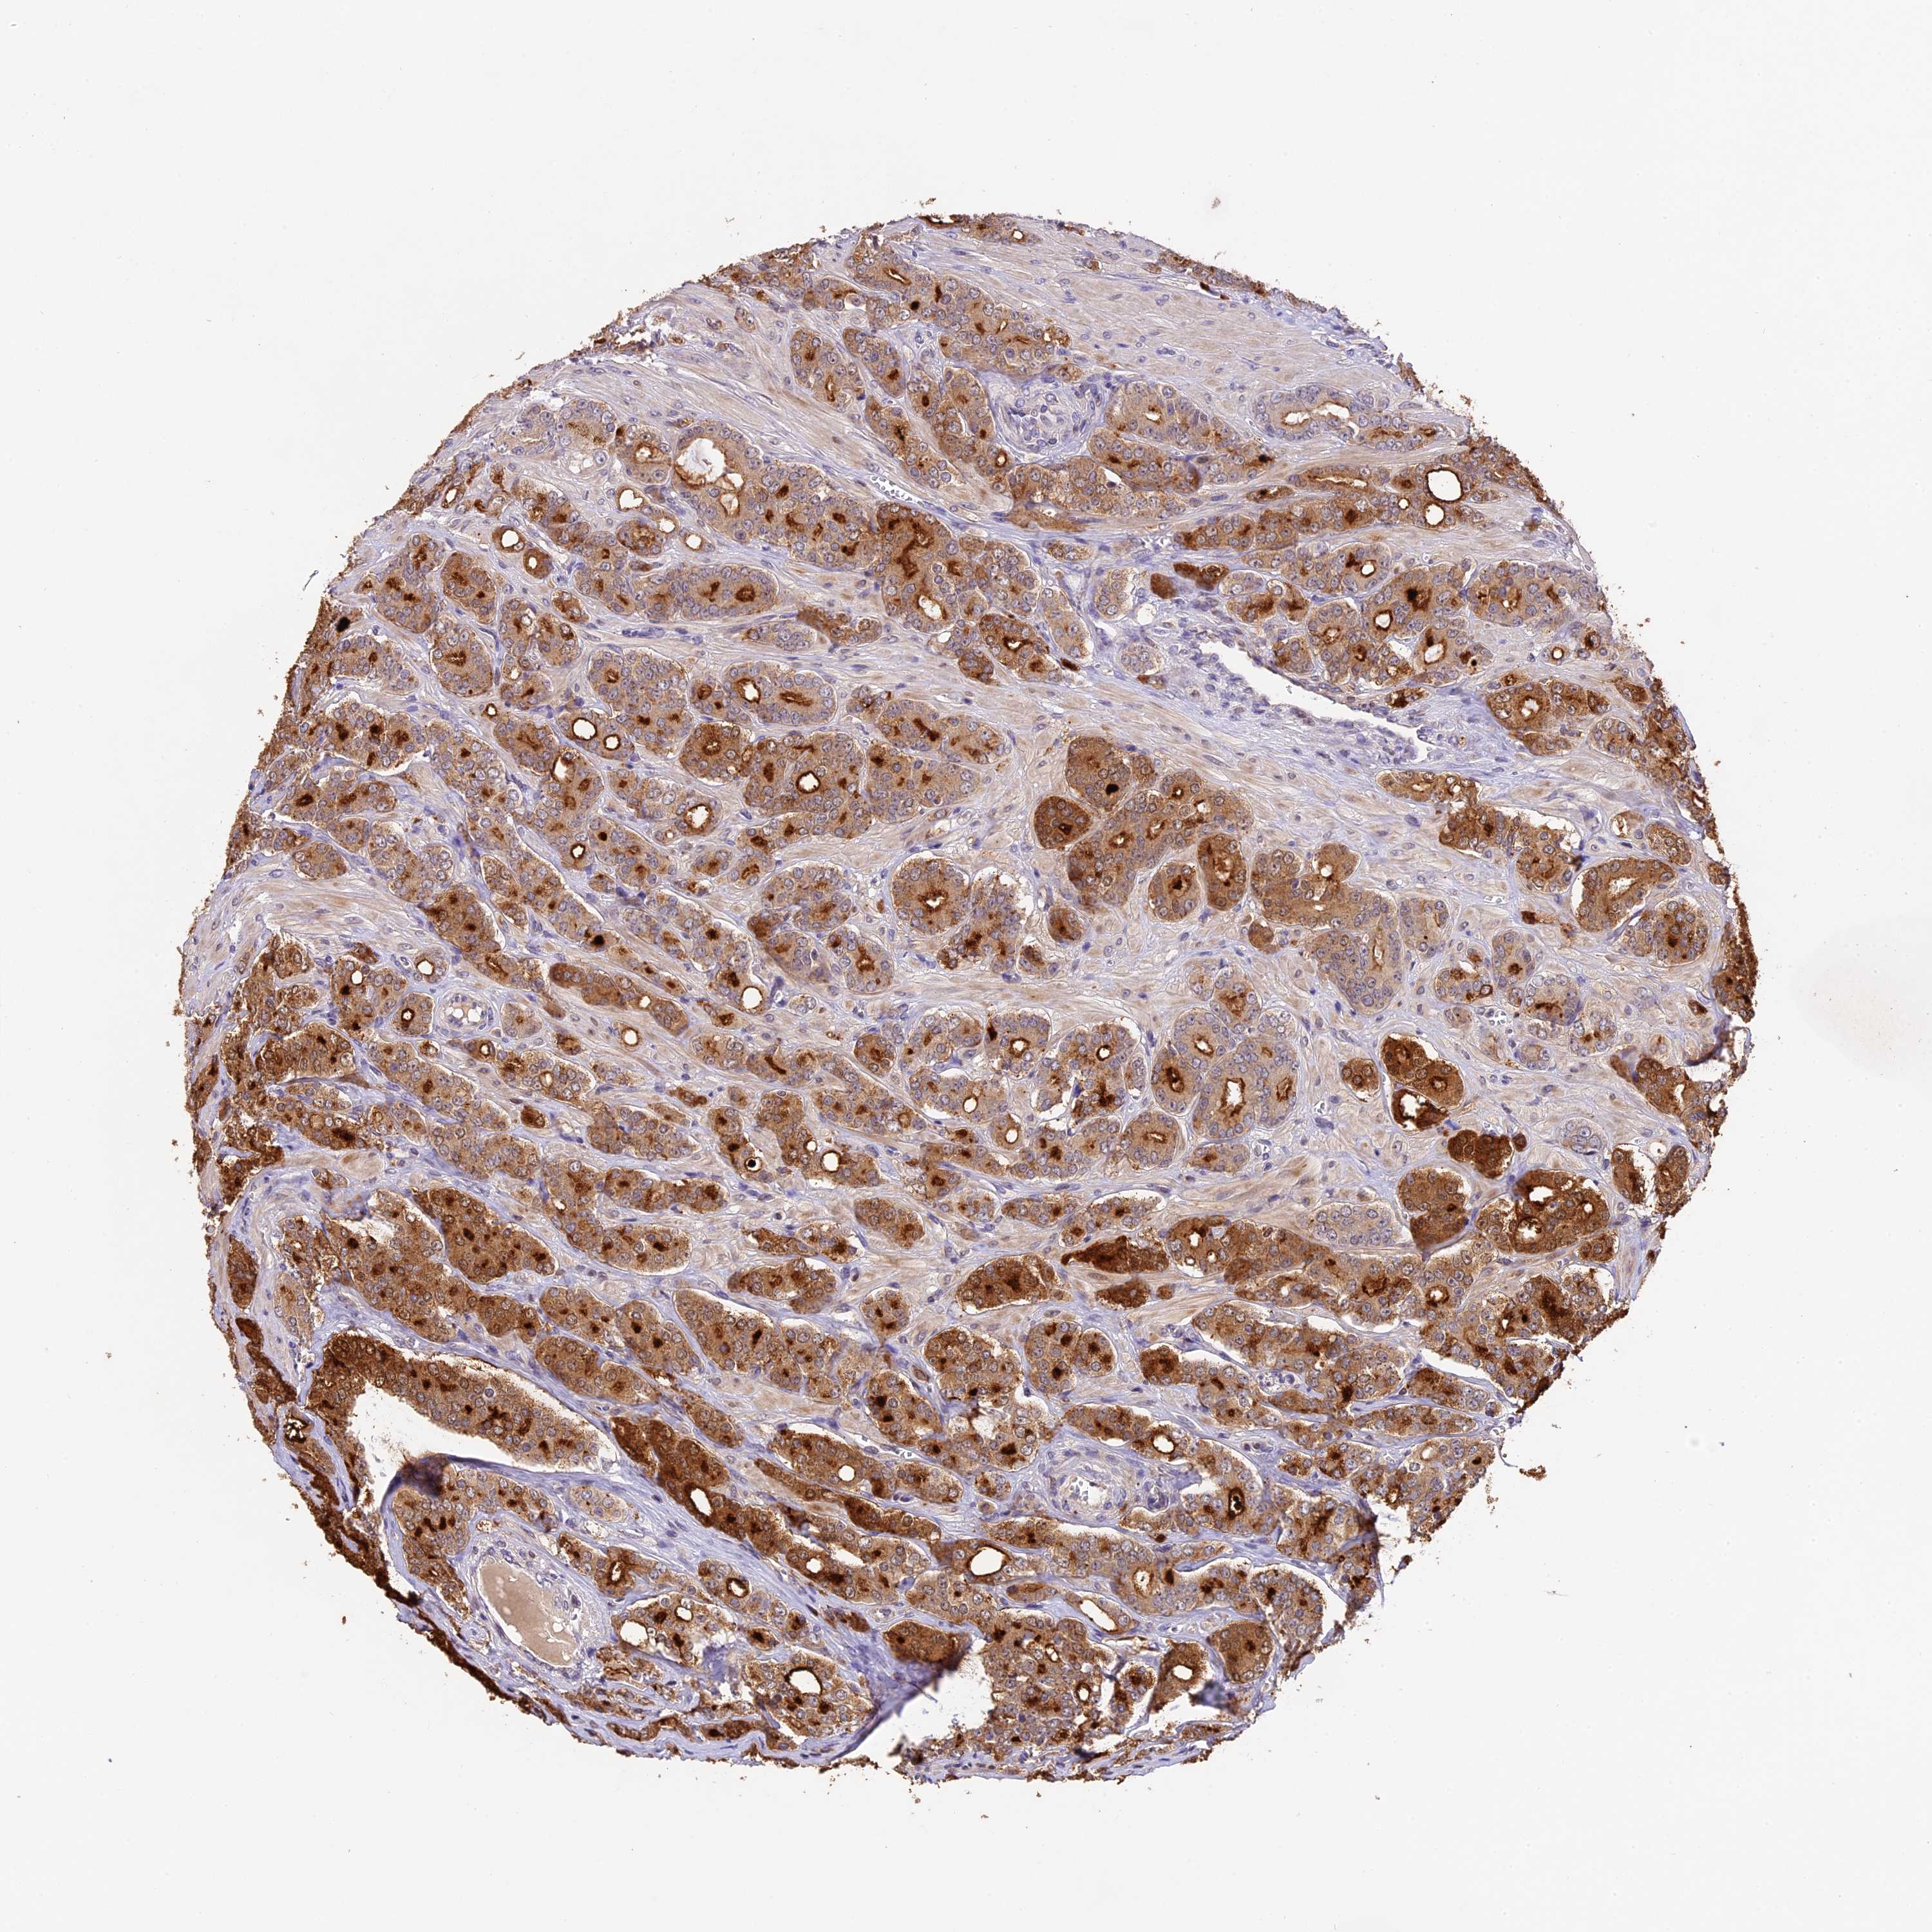

PROSTATE CANCER - Protein expressioni

A mouse-over function shows sample information and annotation data. Click on an image to view it in a full screen mode. Samples can be filtered based on level of antibody staining by selecting one or several of the following categories: high, medium, low and not detected. The assay and annotation is described here.

Antibody stainingi

Antibody staining in the annotated cell types in the current human tissue is reported as not detected, low, medium, or high, based on conventional immunohistochemistry profiling in selected tissues. This score is based on the combination of the staining intensity and fraction of stained cells.

Each image is clickable and will lead to virtual microscopy that enables deeper exploration of all samples and also displays staining intensity scores, fraction scores and subcellular localization as well as patient and tissue information for each sample.

Antibody HPA039533

Antibody HPA040355

Staining

High

Medium

Low

Not detected

Intensity

Strong

Moderate

Weak

Negative

Quantity

>75%

75%-25%

<25%

None

Location

Nuclear

Cytoplasmic/membranous

Cytoplasmic/membranous,nuclear

Adenocarcinoma, High grade

Adenocarcinoma, Low grade